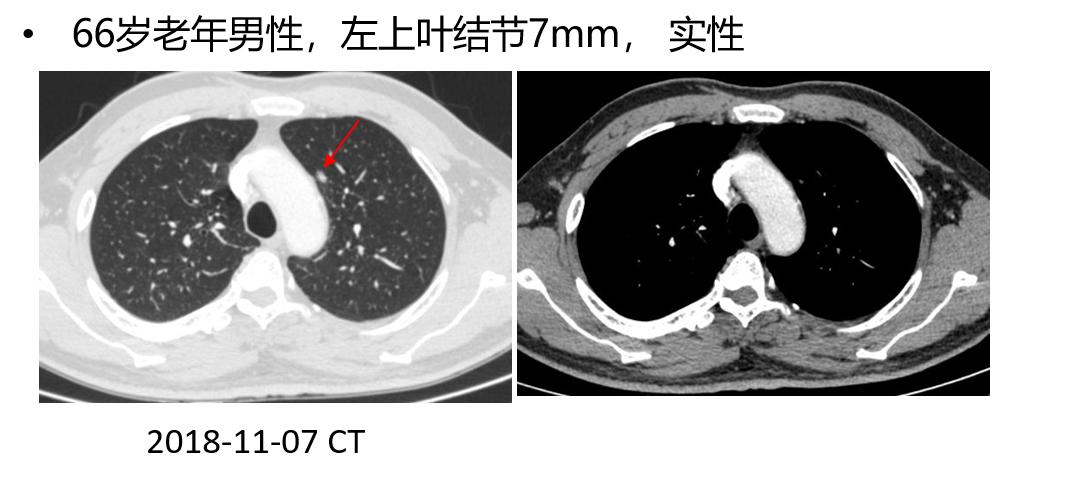

二、支气管镜在周围型肺癌定位中的应用

传统的定位方法都是经皮的,金属勾线、金属线圈、染料标记,但是也可以经支气管镜。

ENB引导下注射ICG胸腔镜术前肺微小病变定位